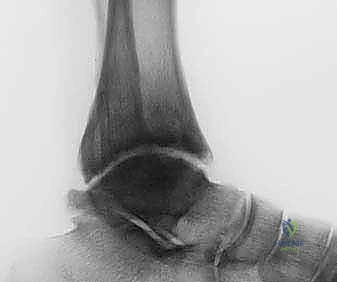

- الأشعة السينية (X-rays) مع الوقوف: لتقييم المسافة المتبقية من المفصل وتحديد درجة الخشونة ومحور الساق.

- الأشعة المقطعية (CT Scan): للحصول على صورة ثلاثية الأبعاد للعظام، واكتشاف أي تكيسات عظمية (Bone cysts) أو نتوءات عظمية (Osteophytes).

- زيادة مساحة المفصل: تظهر الأشعة السينية بوضوح اتساع المسافة بين عظام الكاحل، وهو دليل قاطع على تجدد النسيج الغضروفي.